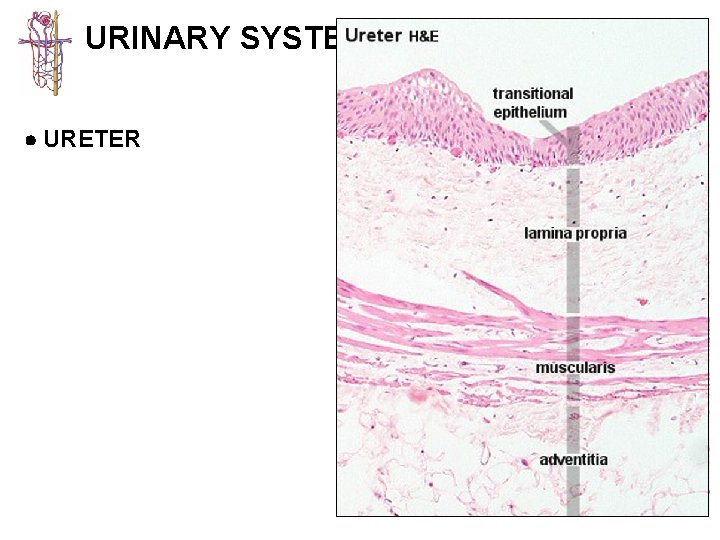

URINARY SYSTEM KIDNEY CALYCES/ URETER BLADDER URETHRA 1 - mucosa lined with transitional 2 -epithelium usually lacking submucosa 3 - muscularis best developed in ureters (2 -3 layers) and bladder (3 layers)

URETER H&E 1: 2: OC IL MUCOSA LAMINA PROPRIA MUSCULARIS ADV

URINARY SYSTEM URETER

URINARY SYSTEM URETER